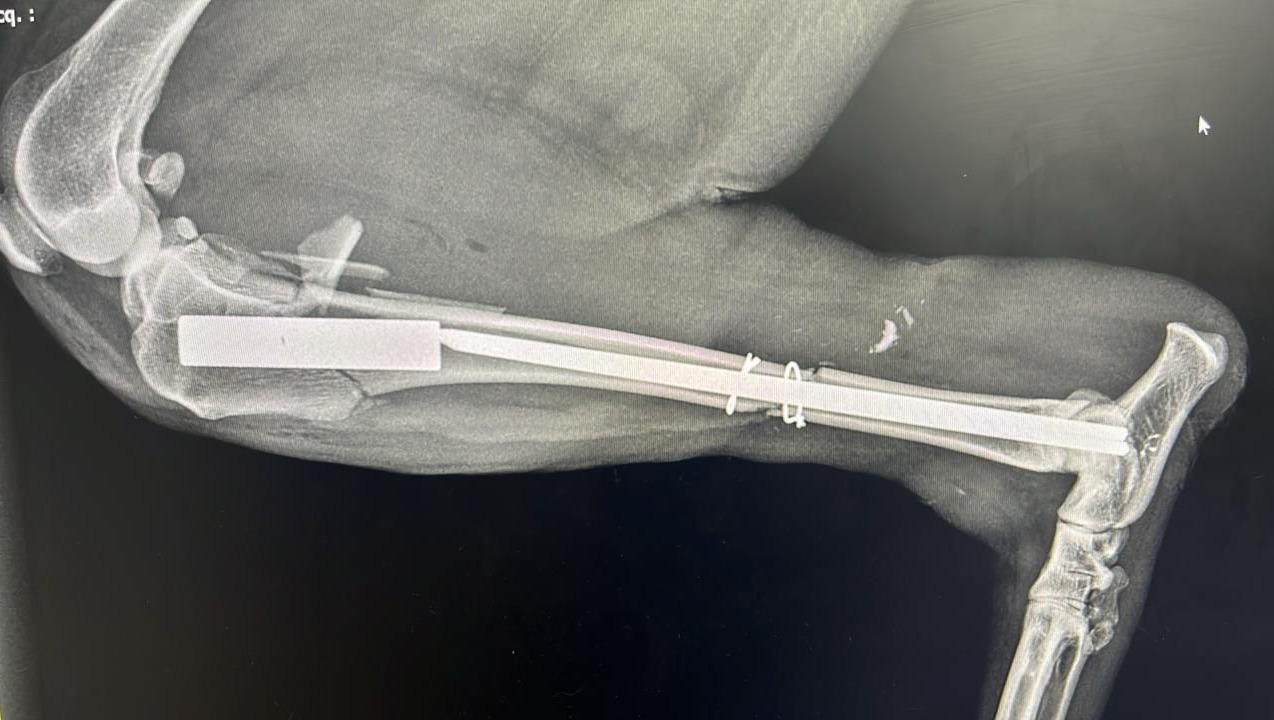

Comme vous pouvez le voir les animaux que nous aidons sont victimes de graves blessures nécessitant des soins vétérinaires très importants.

Ces chiens sont handicapés à vie — certains ont perdu une patte, d’autres deux, certains vivent avec une mâchoire arrachée ou la colonne vertébrale brisée. Malgré leur souffrance, ils nous montrent chaque jour leur incroyable courage et leur soif de vie.

Nous avons déjà investi beaucoup d’argent pour sauver ces chiens de la mort ou d’une vie dans d’horribles souffrances. Aujourd’hui, nous avons besoin de vous pour continuer financer leurs soins vétérinaires : opérations chirurgicales, traitements lourds, rééducation, médicaments, nourriture spécifique… Chaque geste compte pour leur offrir une seconde chance.